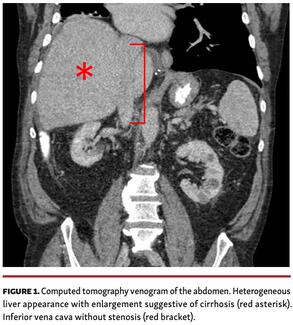

IVC stenosis is a rare complication of bicaval orthotopic heart transplant. IVC stenosis can occur at either the cavo-atrial anastomosis, or the caval cannulation site, with presentations ranging from acute shock early post transplant to a...